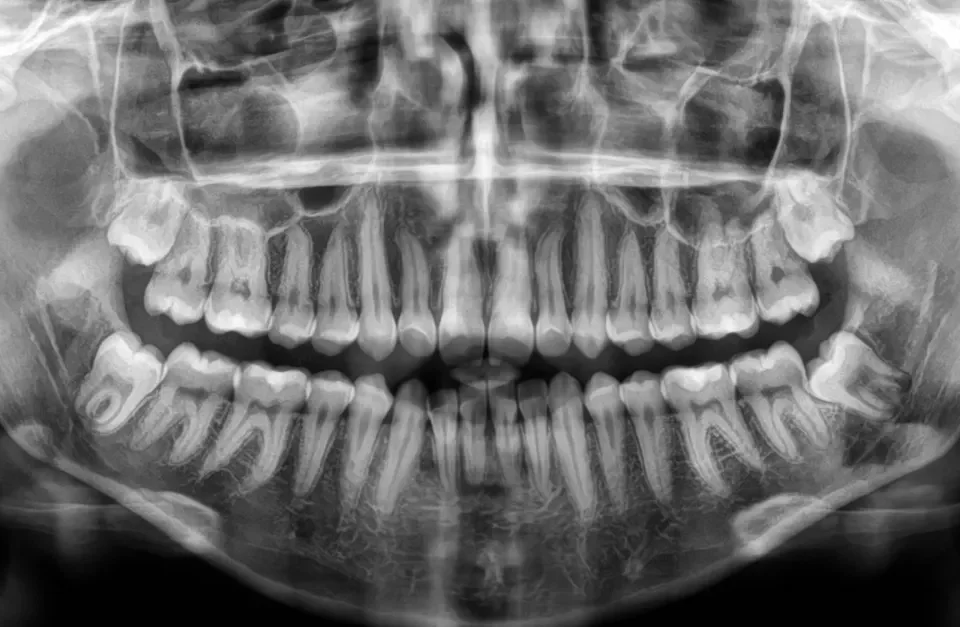

MOSTY ZĘBOWE Wiele osób w pewnym momencie życia staje przed koniecznością usunięcie zęba lub założenia korony ,gdyż własny ząb jest mocno zniszczony. W takim wypadku z pomocą przychodzi lekarz protetyk czyli specjalista w dziedzinie odbudowy zębów na wzór naszych naturalnych. RODZAJE […]